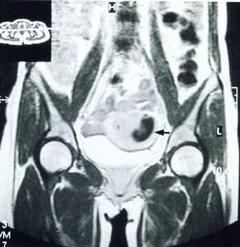

宮角妊娠透視觀察血管性介人治療套用於宮角妊娠的病例較少,其治療方法與宮頸妊娠相似。

宮角妊娠側面透視血管性介入治療

血管性介人治療套用於宮角妊娠的病例較少,其治療方法與宮頸妊娠相似。